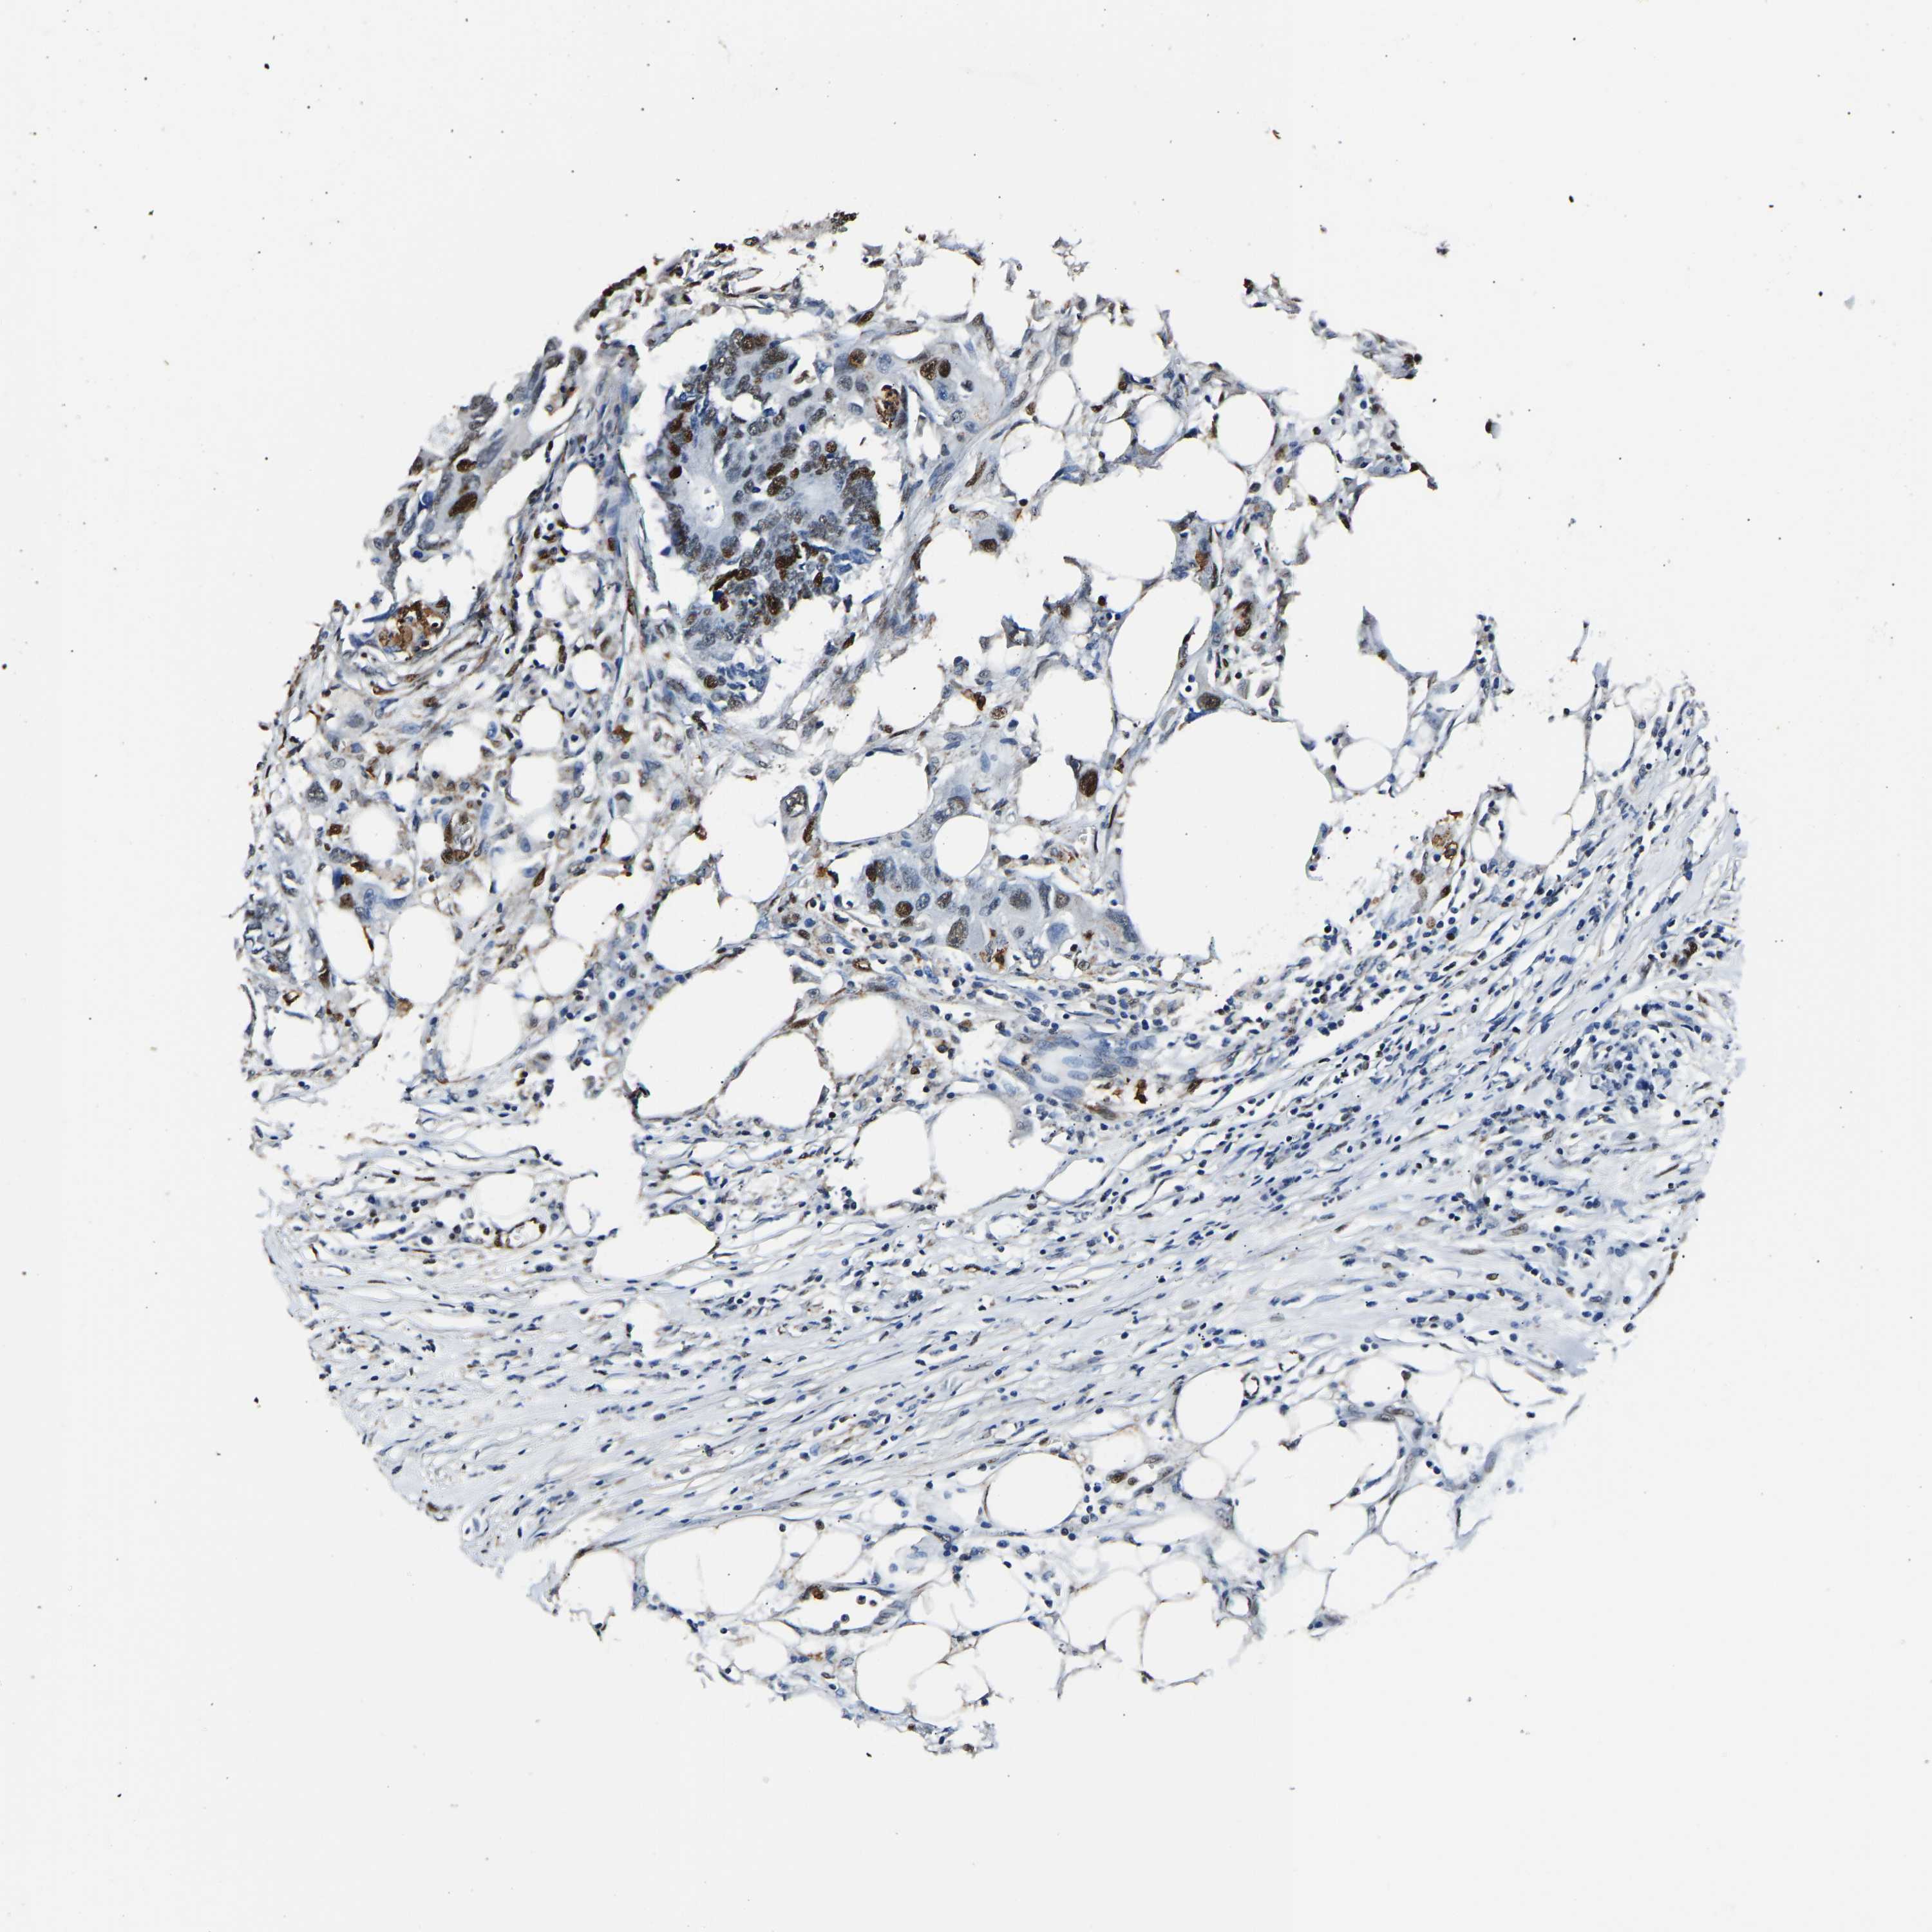

CANCER COLORECTAL CANCER Show tissue menu

Colorectal cancer

Human cancer

Colon adenocarcinoma